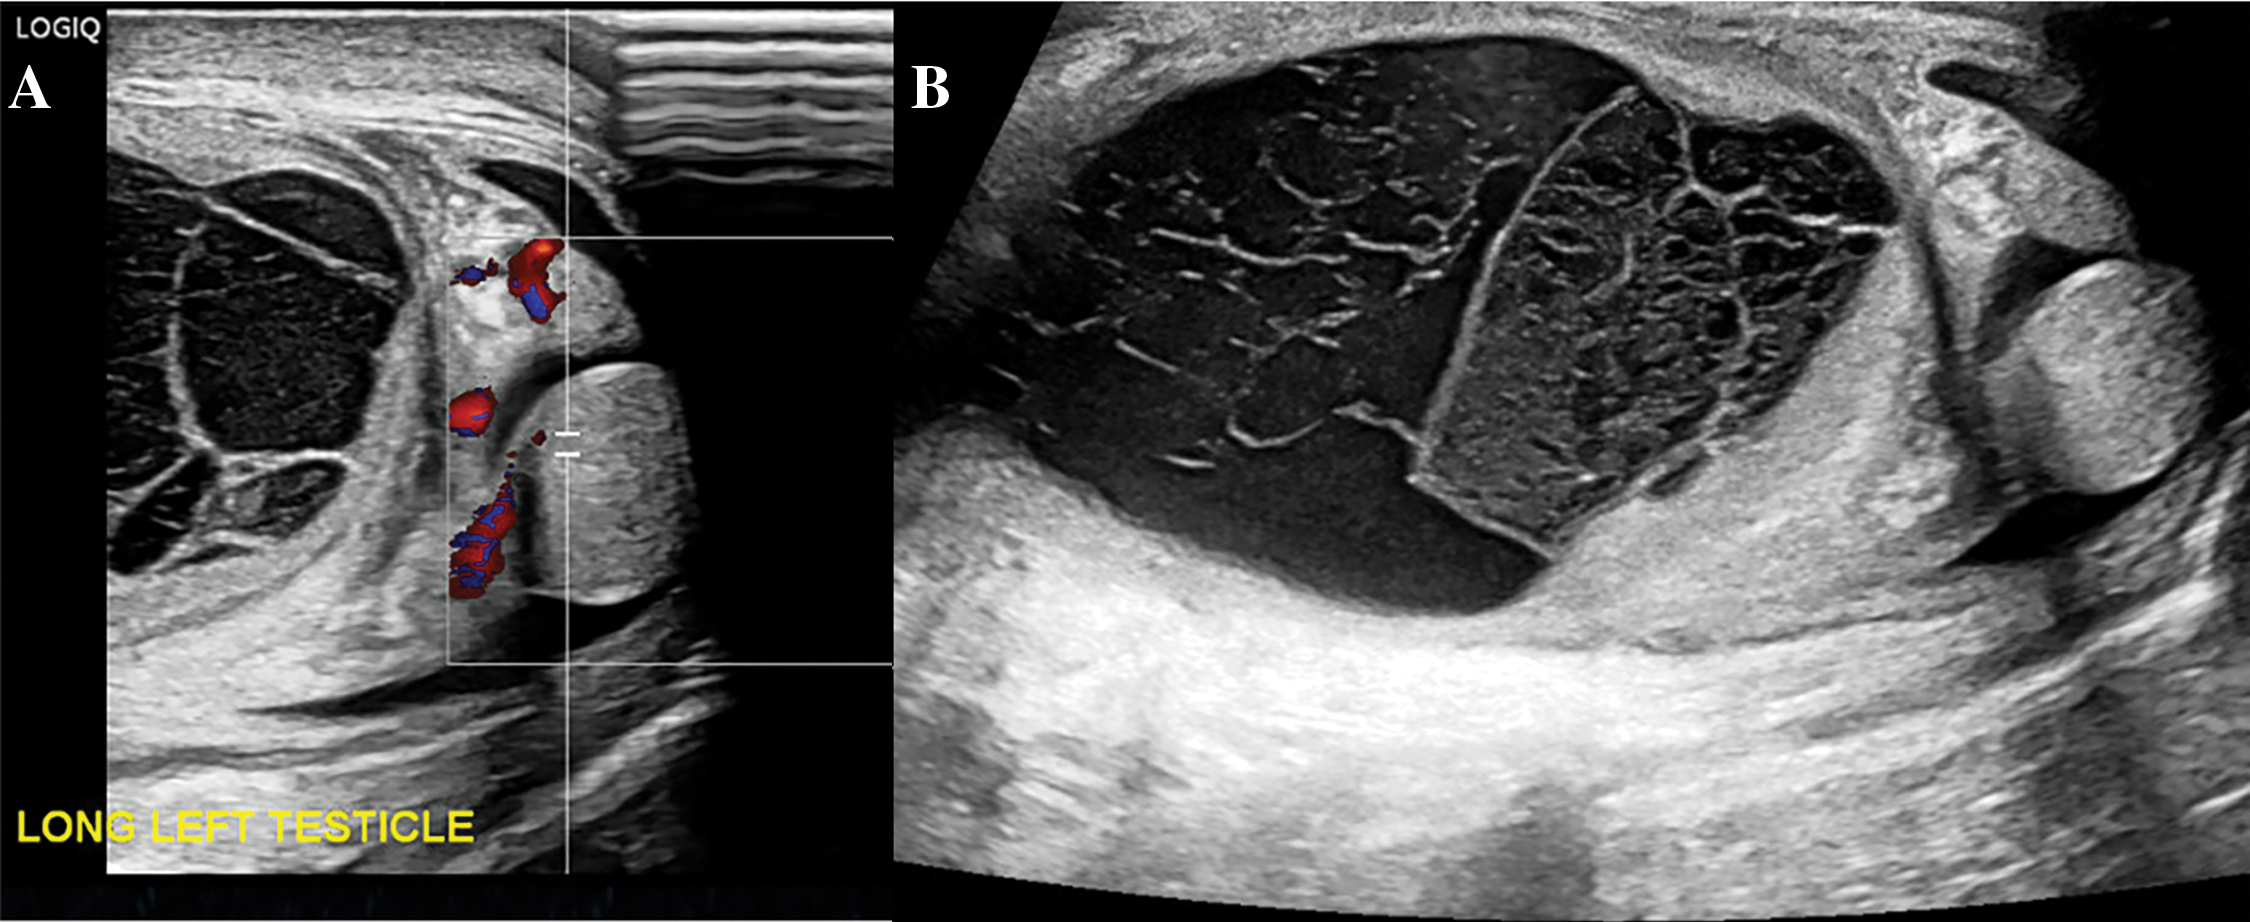

Pediatric Surgery was initially consulted due to concern for an incarcerated inguinal hernia. Point-of-care bedside ultrasound of the left inguinal canal was performed by Pediatric Surgery, and the contents appeared consistent with bowel per their read. Bedside reduction was attempted without success; thus, he was taken to the operating room emergently with Pediatric Surgery for hernia reduction and repair. Time from preliminary diagnosis of incarcerated inguinal hernia to case start was approximately two hours. Diagnostic laparoscopy revealed a closed inguinal ring without hernia and a loculated cystic mass just adjacent to the left ring (Figure 2). The cystic mass was 4 cm × 2.7 cm × 2 cm and dusky red-grey in appearance, with brown hemorrhagic material adherent to the external surface. The structure did not have any association with the bowel. At this point, Pediatric Urology was consulted intra-operatively. Formal intra-operative scrotal ultrasound was obtained, which revealed the left testicle located in the left hemiscrotum without blood flow on color Doppler evaluation (Figure 3A). A large lobulated, multiseptated, complex avascular fluid collection was seen in the left inguinal canal without extension into the peritoneal cavity (Figure 3B). The right testis was retractile but appeared normal (Figure 4).

FIGURE 3. Intraoperative formal scrotal ultrasound findings of the left hemiscrotum. (A) Ultrasound with Doppler highlighting left scrotal testis without flow and enlarged hyperemic epididymis. (B) Ultrasound showing a large, multiseptated left hydrocele

FIGURE 4. Ultrasound with Doppler highlighting the right testis with normal echotexture and blood flow